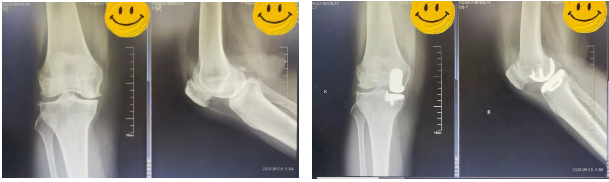

在麻醉科配合下,陈东峰主任手术团队清除了增生的滑膜组织,去除了骨赘,对关节进行了适当松解,术中发现关节面磨损严重,软骨下骨暴露,内侧半月板后角脱位。医生精心安置了人工关节假体,替代了已经损坏的关节面。

手术后无需放置引流管,多模式镇痛下,患者麻醉恢复后即可下地完全负重行走,温女士终于摆脱了困扰她十年的膝痛问题。

术前(左)术后(右)X线光片对比